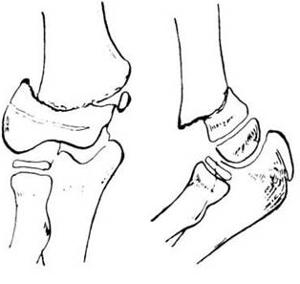

常见四肢骨折的分类之五、Colles骨折

是指发生在桡骨下端3 厘米以内的伸直型骨折,见于中老年有辜质疏松者。由于跌倒时前臂旋前,腕关节背伸,手掌着地,暴力向上传导引起。表现特点:典型的Colles骨折,骨折远端向背侧、桡侧移位,侧面观呈“餐叉”样畸形,正面观呈“枪刺刀”畸形。